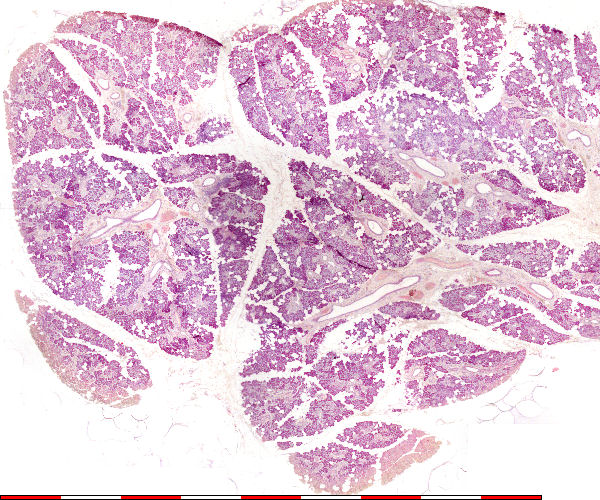

Submandibulêre speekselklier

Submandibular salivary gland

© julie 2008 marius loots